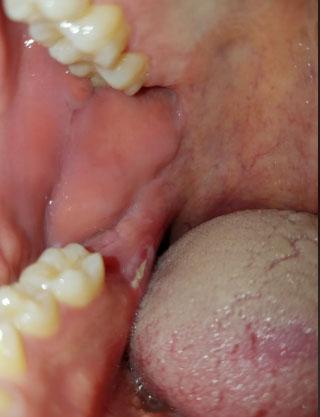

The image shows swelling and redness of the gum tissue near the back teeth, close to the lower molar area. The gum appears raised and irritated, with possible signs of underlying infection or inflammation. The nearby teeth look intact, but the soft tissue suggests a deeper problem beneath the surface.

This type of swelling often indicates gum infection related to a nearby tooth or trapped bacteria.

This case shows localized gum swelling near back teeth, often a sign of infection below the surface. Early dental evaluation prevents infection spread, tooth damage, and serious complications.